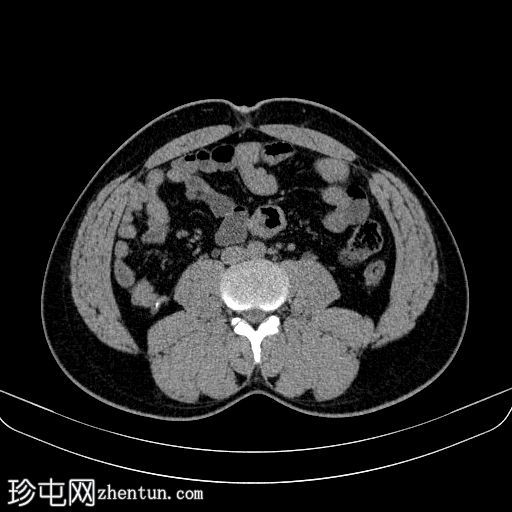

轴位

平扫

双侧肾结石,无梗阻,较大结石位于左侧肾下盏,最大直径约4 mm,平均CT值约730 HU,伴左侧输尿管轻度扩张。

膀胱明显充盈,高度达脐部,若患者无法排尿,可能需要导尿。